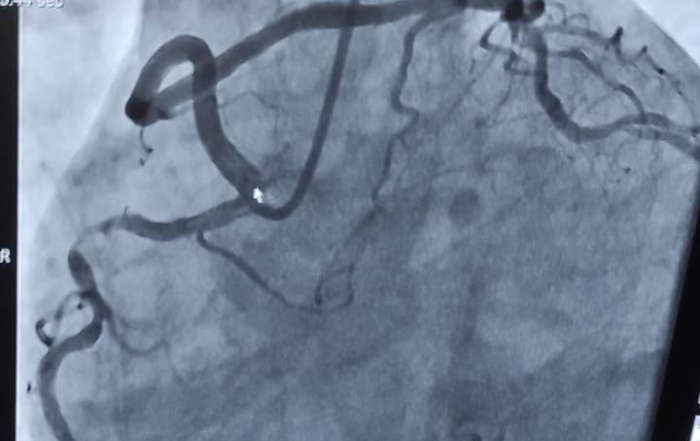

الصحة: اجراء قسطرة تداخلية لحالة نادرة تعاني من جلطة قلبية حادة مع عيوب خلقية في الشرايين التاجية